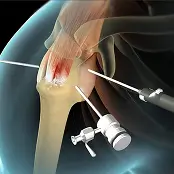

Precision Orthopaedic Surgery to Restore, Optimize, & Preserve.

Advanced orthopaedic care integrating surgical expertise, regenerative medicine, precision diagnostics, and longevity optimization under one roof.

A board-certified orthopaedic surgeon specializing in advanced surgical techniques

Precision Orthopaedics